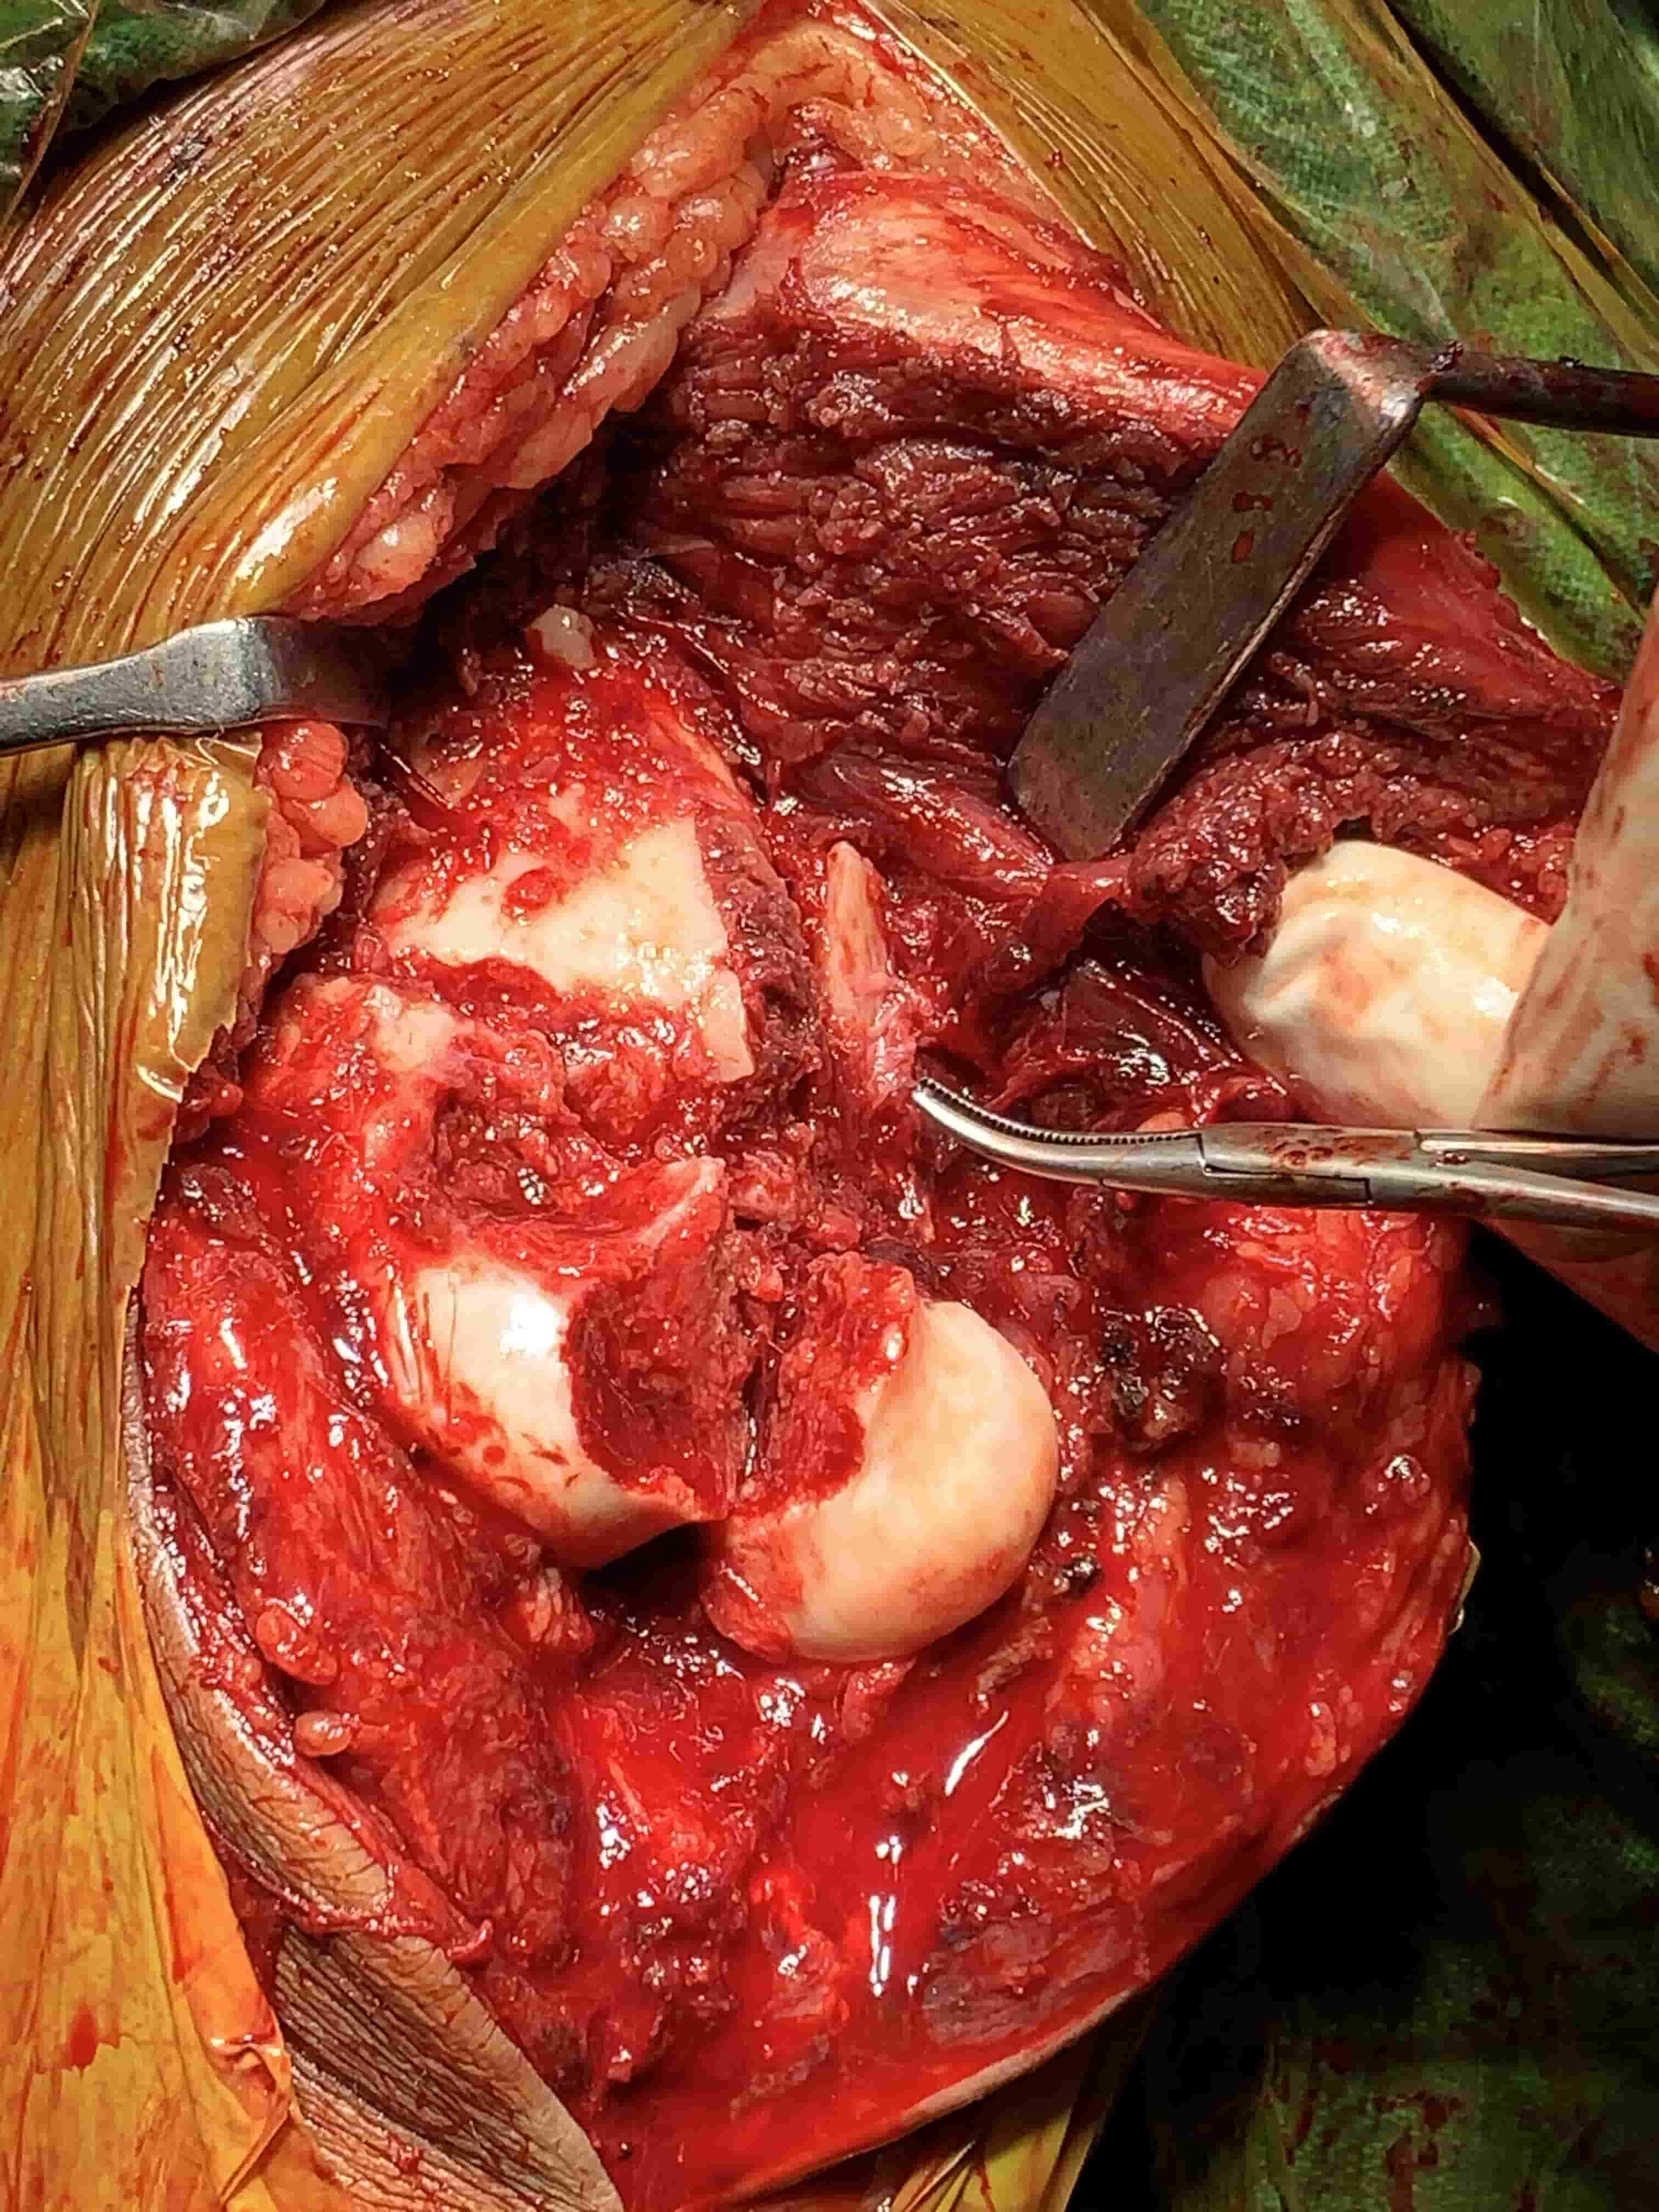

Complex Distal Humerus Comminuted Fracture

Complex Distal Humerus Comminuted Fracture

Complex Distal Humerus Comminuted Fracture

Complex Distal Humerus Comminuted Fracture

Complex Distal Humerus Comminuted Fracture

Complex Distal Humerus Comminuted Fracture

Complex Distal Humerus Comminuted Fracture

Complex Distal Humerus Comminuted Fracture

Complex Distal Humerus Comminuted Fracture

Complex Distal Humerus Comminuted Fracture

Complex Distal Humerus Comminuted Fracture

Complex Distal Humerus Comminuted Fracture

Complex Distal Humerus Comminuted Fracture

Complex Distal Humerus Comminuted Fracture